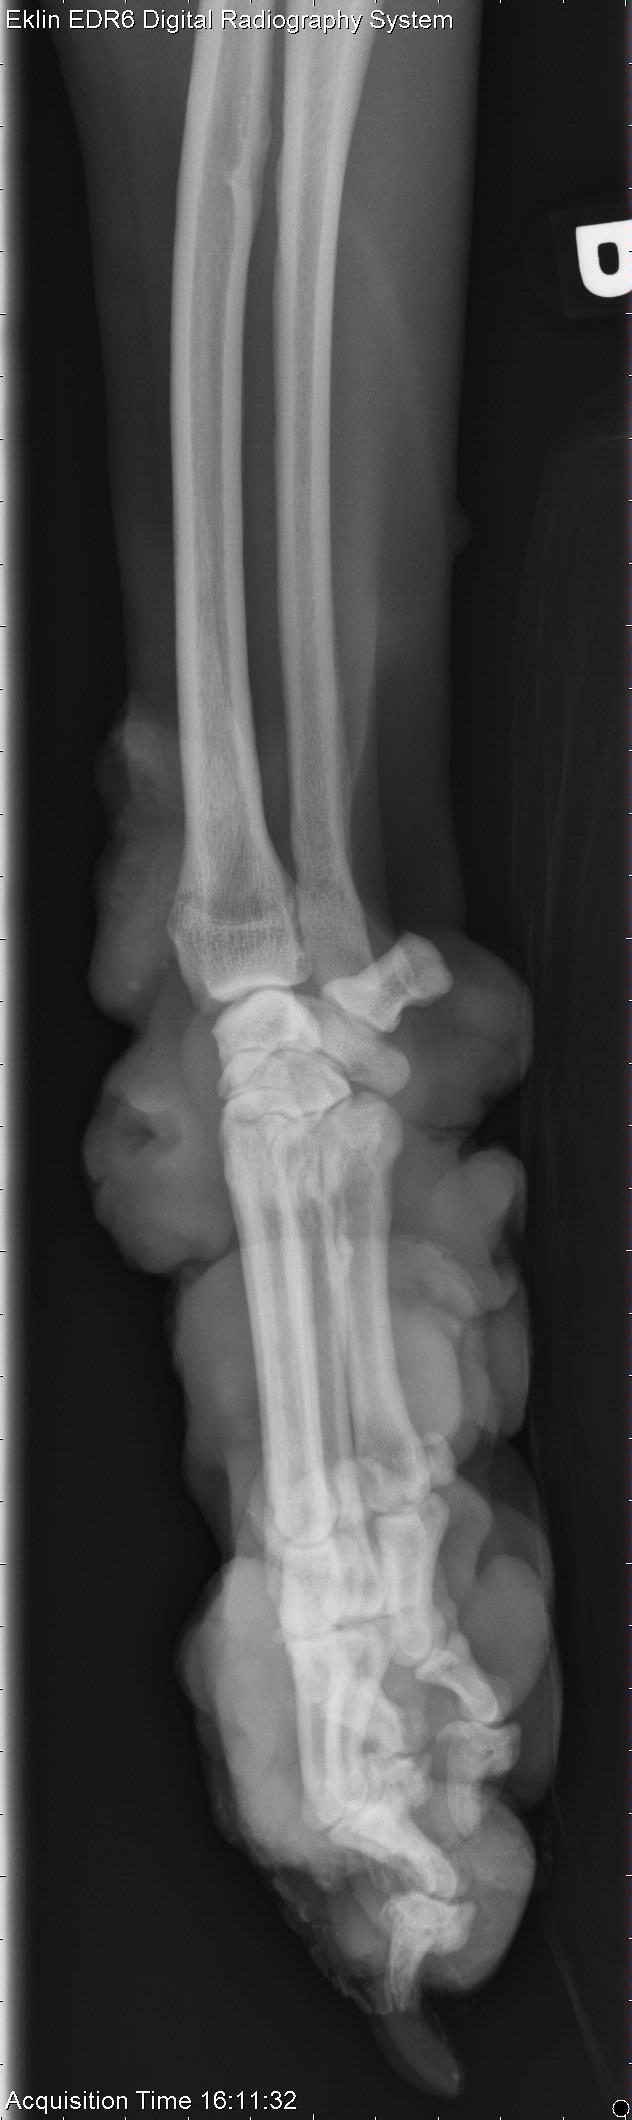

The last case of the year is 10-year-old male Boxer with swelling on the thoracic wall and right thoracic limb. What are your findings and differential diagnoses?

Thoracic Limb-R AP Fore

Thoracic Limb-R LAT Fore

There are multiple thickened regions of soft tissue surrounding the right carpus. Many of these swellings have air-filled cavities on the surface indicating ulceration. There is irregular to pallisading periosteal new bone formation along the medial aspect of the proximal phalanx of the second digit. The phalanx of the first digit is irregularly margined and tapers to a sharp osseous projection, with a small mineral opacity seen just distal to this phalanx. There is smoothly margined periosteal new bone formation along the medial aspect of the mid-diaphysis of the right 3rd metacarpal bone. There is also smoothly margined, periosteal new bone formation along the mediocaudal aspect of the distal radial diaphysis.

The soft tissue changes are consistent with neoplasia, likely an additional site to that seen on the thoracic wall. The ulceration may have resulted in osteomyelitis, or periostitis of the adjacent bone. Neoplastic extension into the bone could also be considered.

• Non-epitheliotrophic cutaneous T-cell lymphoma (large cell)